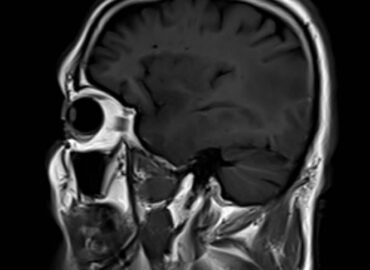

Hombre de 70 años, es llevado por familiares a guardia con trastorno del lenguaje, disartria y anosmia.